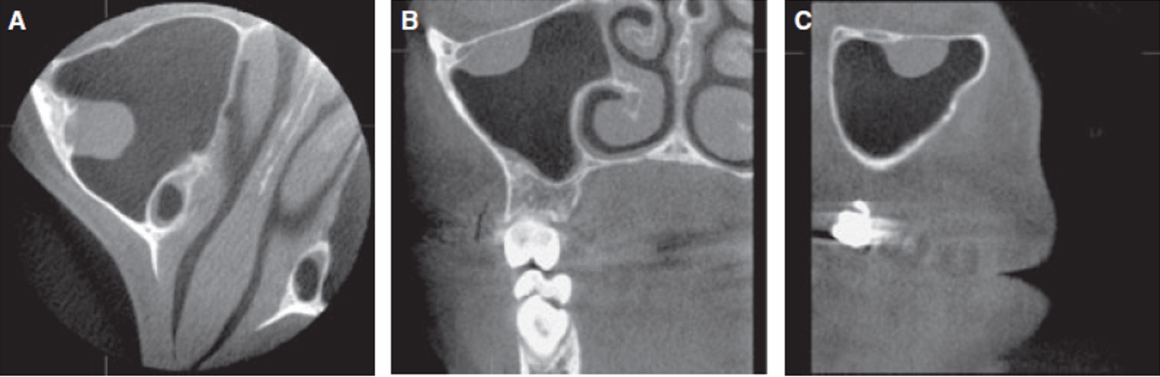

Fig.1

Un informe de caso describió el descubrimiento incidental de un aneurisma intracraneal potencialmente mortal en una TCCB realizada con fines dentales. En otro caso clínico, se diagnosticaron fisuras medias de las vértebras cervicales en una tomografía TCCB realizada con fines ortodónticos. Un estudio reciente evaluó los hallazgos incidentales en 500 tomografías TCCB con un campo de visión amplio realizadas con indicaciones ortodónticas, de ATM, endodónticas y de implantes. En este estudio, se informó de una tasa global de hallazgos incidentales del 24,6 % para el grupo de ortodoncia. Utilizando imágenes por resonancia magnética para analizar los cambios incidentales en la mucosa paranasal, se informó de la mayor prevalencia en los senos etmoidales, seguidos de los senos maxilares. Los senos maxilares tuvieron una prevalencia de engrosamiento mucoso superficial o plano que osciló entre el 23 y el 31 %, y una prevalencia de lesiones quísticas que osciló entre el 7 y el 10 % (14). la membrana de Schneider en CBCT limitadas realizadas para ortodoncia en pacientes asintomáticos. Los parámetros de resultado secundarios fueron el análisis de una posible correlación entre estos hallazgos y la edad y el sexo de los pacientes, el campo de visión de la CBCT y la estación del año (invierno ⁄ primavera ⁄ verano ⁄ otoño) durante la cual se realizó la radiografía.